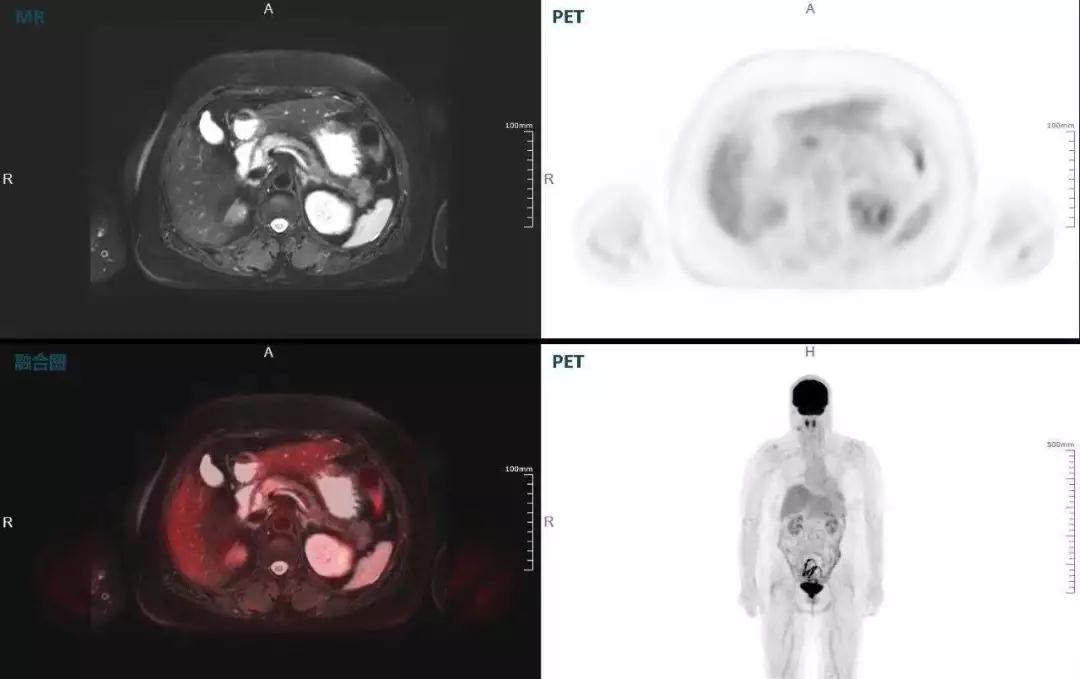

聯(lián)影“時(shí)空一體”超清TOF PET/MR搭載的壓縮感知技術(shù),能夠同時(shí)實(shí)現(xiàn)16期成像,精準(zhǔn)捕獲肝臟動(dòng)態(tài)影像的每一瞬間,同時(shí)兼顧早期與晚期等全部期相的完整病灶信息,實(shí)時(shí)、全方位鎖定病灶。同時(shí),基于其2.8mm超高分辨率,能夠精細(xì)呈現(xiàn)腫瘤邊界信息,捕捉局部微小病灶與遠(yuǎn)端轉(zhuǎn)移灶,助力醫(yī)生精準(zhǔn)診斷。

(對(duì)于同一例肝臟惡性腫瘤,PET-CT與PET/MR成像對(duì)比??梢钥吹?,聯(lián)影PET/MR圖像對(duì)腫瘤邊界和FDG高濃聚區(qū)域清晰顯示。)

中山醫(yī)院核醫(yī)學(xué)科在臨床實(shí)踐中發(fā)現(xiàn),基于聯(lián)影“時(shí)空一體”超清TOF PET/MR,不僅解剖信息和代謝信息能夠完美融合呈現(xiàn),同時(shí)精細(xì)展示局部病灶與周圍組織的復(fù)雜關(guān)系,并能全盤檢測(cè)病灶的全身轉(zhuǎn)移,為醫(yī)生臨床診斷提供更豐富信息。

(胰腺腫瘤,MR顯示胰腺體部信號(hào)異常,PET顯示稍高攝取,結(jié)構(gòu)改變和功能異常提示胰腺M(fèi)T可能大。)